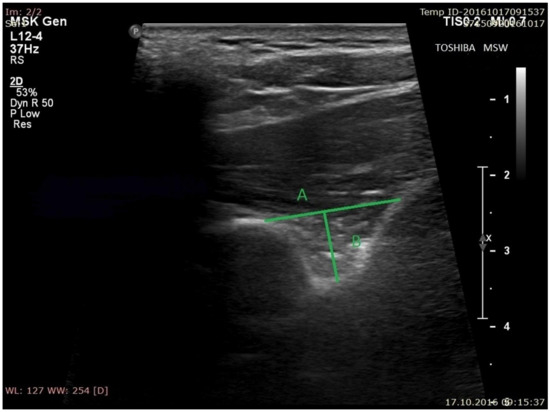

- the superior transverse diameter (STD) of the suprascapular notch: the maximal distance in the horizontal plane between the corners of the suprascapular notch (Figure 2).

- the maximal depth (MD) of the suprascapular notch: the distance between the STD and the deepest point of the suprascapular notch measured in a plane perpendicular to the STD (Figure 2).